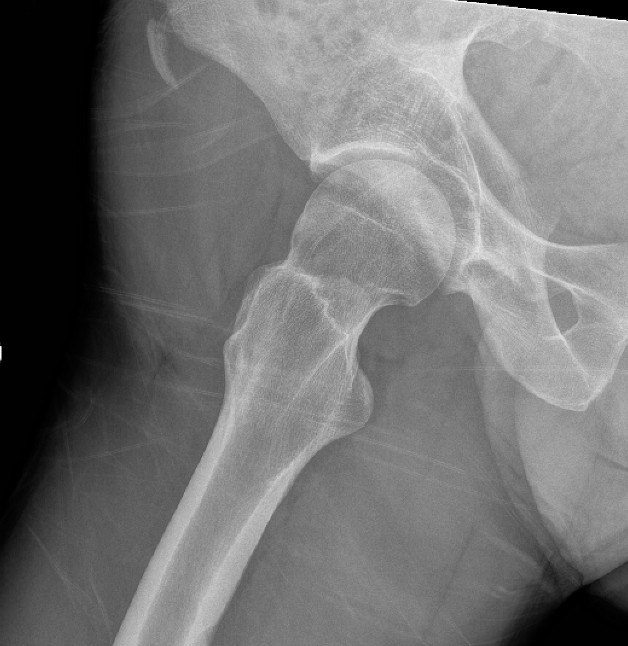

ASIS Avulsion

Attachments

Sartorius & Tensor fascia lata

Imaging

ASIS displaced 1ASIS displaced 2